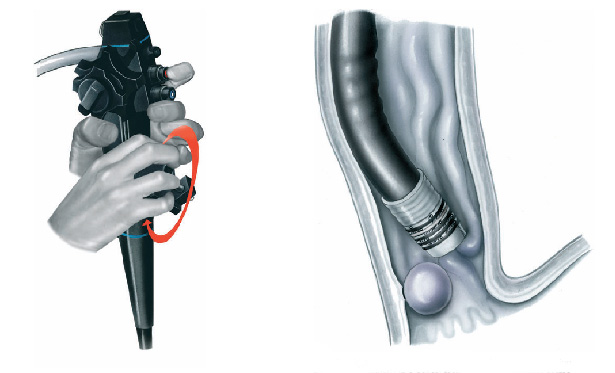

Após o preparo do cólon, o paciente é levado à sala de exame onde será sedado. A sedação é realizada por via endovenosa e ajuda o paciente a dormir e relaxar. O colonoscópio é então introduzido pelo reto até o ceco (porção inicial do cólon) ou até o íleo terminal (porção final do intestino delgado). Durante a retirada do aparelho é feita uma minuciosa inspeção identificando as eventuais alterações.

Pacientes que têm o objetivo de emagrecer, podem ter como alternativa a passagem de um balão intragástrico. A passagem do balão é realizada por endoscopia e o procedimento dura cerca de 20 a 30 minutos.

Passagem de Balão Intragástrico

1. O balão intragástrico é introduzido desinsuflado durante a endoscopia e colocado no estômago.

2. Um líquido azul (azul de metileno diluído em soro fisiológico) é colocado dentro do balão através de uma válvula. O volume varia entre 500-700 ml.

3. O aparelho de endoscopia é removido e o balão intragástrico pode ser deixado por um período de até 6 meses.

O que acontecerá durante o exame ?

Após o preparo do cólon, o paciente é levado à sala de exame onde será sedado. A sedação é realizada por via endovenosa e ajuda o paciente a dormir e relaxar. O colonoscópio é então introduzido pelo reto até o ceco (porção inicial do cólon) ou até o íleo terminal (porção final do intestino delgado). Durante a retirada do aparelho é feita uma minuciosa inspeção identificando as eventuais alterações.

Pacientes que têm o objetivo de emagrecer, podem ter como alternativa a passagem de um balão intragástrico. A passagem do balão é realizada por endoscopia e o procedimento dura cerca de 20 a 30 minutos.

Passagem de Balão Intragástrico

1. O balão intragástrico é introduzido desinsuflado durante a endoscopia e colocado no estômago.

2. Um líquido azul (azul de metileno diluído em soro fisiológico) é colocado dentro do balão através de uma válvula. O volume varia entre 500-700 ml.

3. O aparelho de endoscopia é removido e o balão intragástrico pode ser deixado por um período de até 6 meses.